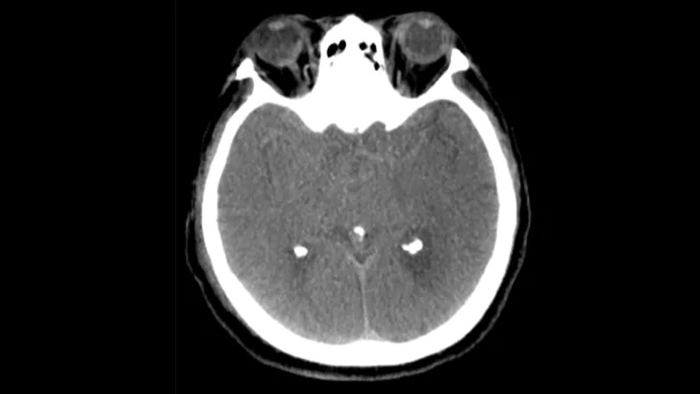

Drei SmartCT Aufnahmen

CT-artige Darstellung

SmartCT Soft Tissue generiert eine CT-artige Darstellung des Weichgewebes und erleichtert die Schlaganfalldiagnose auf drei Arten: Ein kontrastmittelfreier Scan hilft bei der Erkennung früher ischämischer Veränderungen. Ein Scan der frühen Phase hilft bei der Identifizierung des proximalen Verschlusses. Ein kontrastmittelverstärkter Scan der Spätphase unterstützt die Erkennung von Kollateralen.